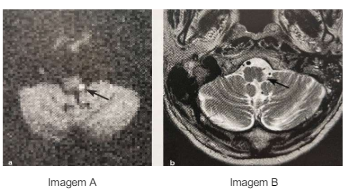

Imagem A: Difusão com restrição na parte dorsolateral esquerda do bulbo Imagem B: T2 com hiperintensidade na parte dorsolateral esquerda do bulbo.